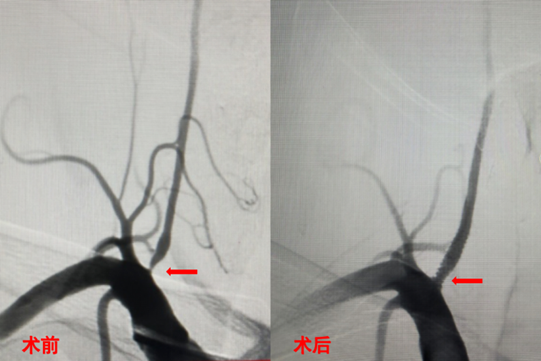

病例2:男,58岁,因“头晕8个月,加重伴左侧肢体麻木1天”就诊,脑血管造影示“右侧椎动脉V1段重度狭窄”,行右侧椎动脉支架置入术,术后狭窄处恢复良好,患者的症状明显缓解。